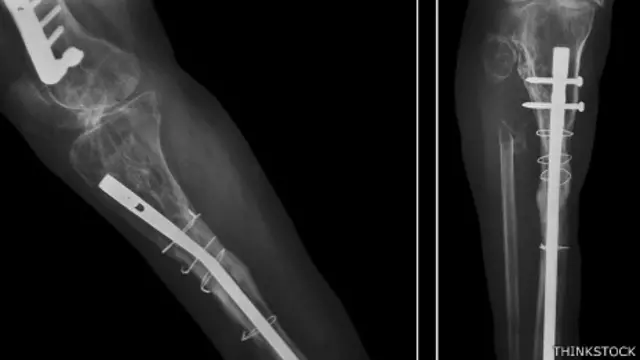

Uno de los tratamientos para las fracturas de hueso es colocar una placa o tornillo a fin de ayudarlo a sanar. Pero, ¿qué pasa cuando se trata de la cara o hay complicaciones con el material implantado?

Los metales que se usan comúnmente tienen la desventaja de que pueden causar estrés en el hueso, suponen un riesgo de infección o incluso pueden provocar una fractura durante el proceso de sanación, lo que supone someter al paciente a una segunda operación.

Otras de las ventajas de este material es que no se ve en los rayos X, lo que -según el experto- puede ayudar a los cirujanos a ver cómo va progresando la fractura en el período posoperatorio, sin metales que le tapen la vista.